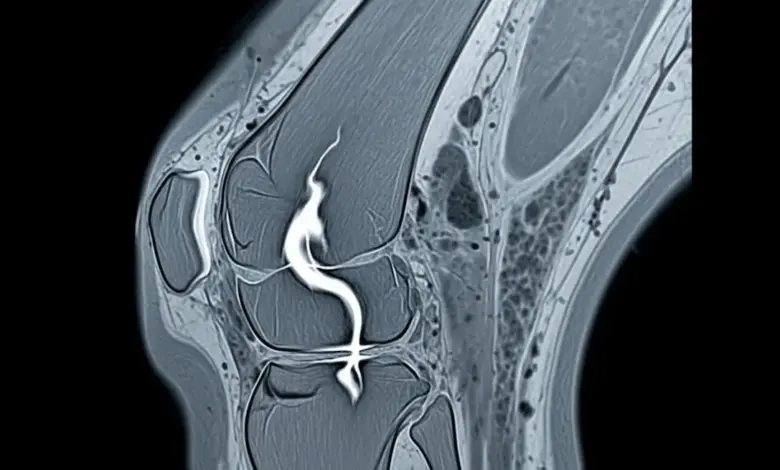

Os exames de imagem ajudam a confirmar a suspeita e a definir a extensão da ruptura. Os mais usados são:

- Ressonância magnética.

A ressonância tem um papel importante quando existe dúvida clínica ou necessidade de avaliar melhor o padrão da lesão.